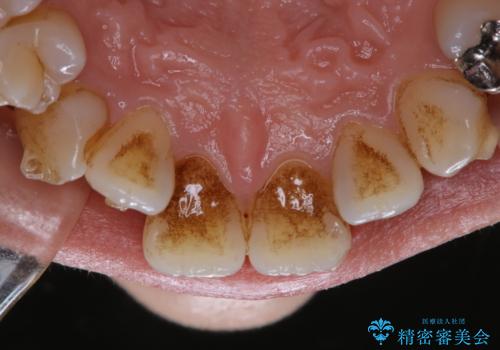

- インビザライン矯正治療中に頑固に付着した着色を取りたいとのことでした。PMTC60分コースを行いました。

アタッチメントが歯に付くと、表面が凸凹し磨き残しが多くなったりと、プラークや歯石・着色がつきやすくなることがあります。

※着色や歯石の量、お口の状態により60分コースでも全ての汚れを除去することができない場合もあります。